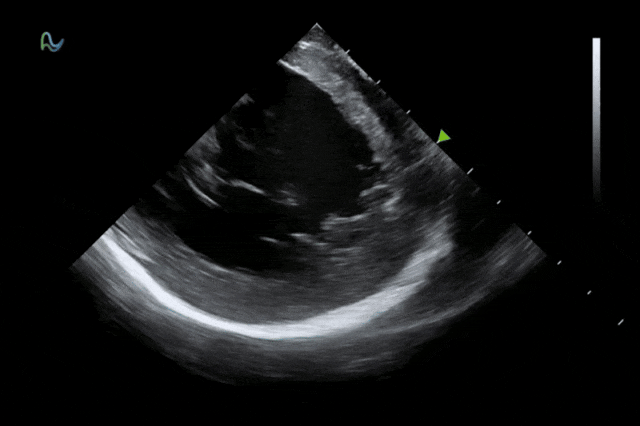

心腔内超声(ICE)被誉为心脏介入手术的"黄金眼",能够顺利获得微创方式实时呈现心脏内部结构和血流成像,为房颤消融、左心耳封堵、先心病介入等手术给予精准成像导航。相较于传统影像手段,ICE具有无辐射、实时成像、操作灵活等显著优势,已成为国际指南推荐的核心诊断技术。

本次获批的ICE导管在全球首次采用了80阵元大孔径高密度探头设计,较传统普通的64阵元产品大幅度提升了成像分辨率、成像深度和图像对比度,可清晰辨识心脏细微结构和血流,为复杂手术给予更可靠的超声成像支持。同时,8F导管凭借更小的外径,显著提升导管顺利获得性和操控性,对病人创伤更小,尤其适合血管条件受限或小心脏患者;10F导管则凭借其优质的成像质量,为复杂心脏介入手术给予精准的影像引导。